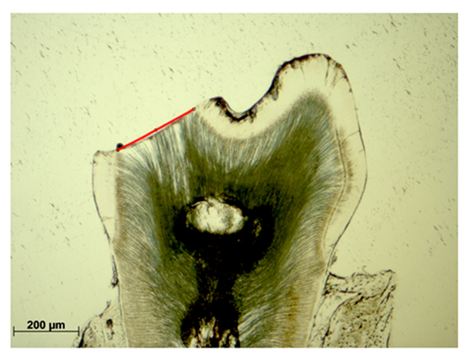

Enamel-free areas

Enamel-free areas were documented, both, in WT and Cobl KO histological sections. In addition, defects were precisely measured by straight lining of the exposed dentin contour (Figure 2, red line).

In some samples of both groups, enamel-free areas were observed as well. These defects usually occurred isolated in the oral or vestibular cusps region (Figure 6). In all specimens no more than two enamel-free areas occurred simultaneously. It was verified that those defects were more frequently detected in Cobl KO samples as compared to WT. In detail, WT showed a mean defect number of 0.401 relatively to the total number, while in Cobl KO the value increased to 0.769. Both results differed significantly (p<0.001). Furthermore, it was found that enamel-free defects in the cusps regions occurred by an increased probability of 1.323 in Cobl KO animals (p=0.004). In addition, the size of each enamel-free defect was exactly measured. Compared to WT, defects tended to be enlarged in Cobl KO samples. In detail, a mean defect size of 0.19 ± 0.11 mm was determined for WT samples, while in Cobl KO specimens the value increased to 0.22 ± 0.15 mm. However, direct comparison of both groups did not reveal any significant difference among both defect sizes (p=0.51, Figure 5(c)).